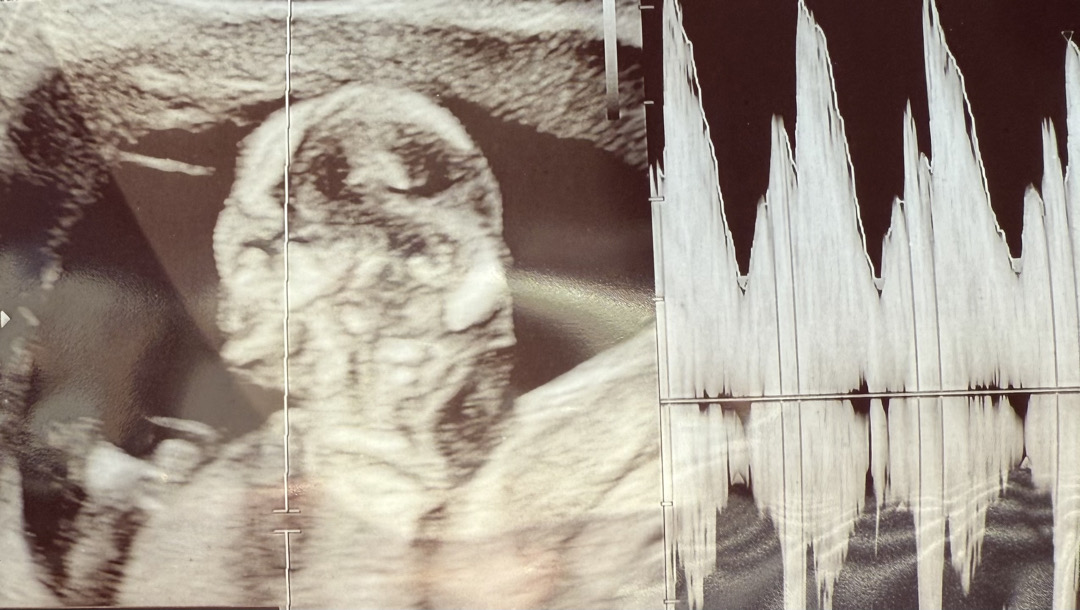

1차 기형아 검사할때 목투명대는 정확히 재신거 같고 코뼈는 따로 이야기안하시고 코가 이렇게~있다고만 이야기하시고 넘어가셨는데 어제 병원갔다가 초음파봤는데 사진에서 코가 제대로 안보이는거 같아서요 ㅠㅠ 다들 어떻게 보이시나요..?

저 초음파가 옆모습인거죠? 캡쳐된 장면이 잘못나온건지 뭔지는 몰라도 1차기형아 검사했던 제 12주 초음파랑은 다르긴 한데요....? 물론 담당 선생님이 아무이상 없다고 하신거면 괜찮긴 하겠지만요! 저는 12주3일에 촬영했고 코뼈 또렷하게 보였어요